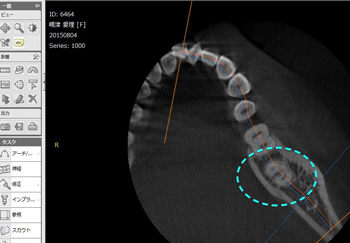

手術時間は「1時間以内」が条件(午後診が始まるまでの間)となるためCT画像で親知らずを縦分割、横分割にして歯の形状を分析して、最短時間での抜歯の準備を行う。

上記の3D画像からも分かるように内側(舌側)への傾斜もきつかったため、歯を分割する際、「舌を傷つけない」事に最も気を配りました。